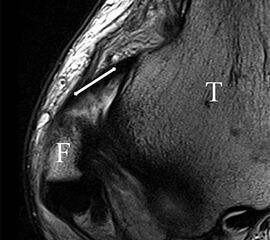

Bezogen auf die Transversalebene verläuft die Syndesmose ca. 30° schräg cranio-caudal anguliert (Abb. 15 a). Häufig lassen sich drei Hauptfaszikel differenzieren: das kürzeste superiore, das stärkste mittlere und das längste kaudale Faserbündel. Ein akzessorisches Bündel, das anteriore-inferiore, tibiofibulare Ligament (AITFL) oder auch Bassett-Ligament wird in 80-94% der Patienten nachgewiesen 8. Dies weist einen unmittelbaren Bezug zur anterolateralen Talusschulter auf (Abb. 17). In Kombination mit einer Außenbandinstabilität und konsekutivem, talarem Vorschub kann dieses zu einem Impingement an der anterolateralen Taluskante führen mit nachfolgender chondraler oder osteochondraler Läsion.

Jedoch findet man sich auch hier mit dem Problem der in den Standard-Projektionen schräg verlaufenden Syndesmose konfrontiert. Der oligofaszikuläre Aspekt der vorderen Syndesmose kann in der axialen Schnittebene eine zum Verwechseln ähnliche Morphologie wie eine Ruptur aufweisen (Abb. 15 b und c). Doppelangulierte Schnitte entlang der Achse (schräg koronar/schräg sagittal) lassen hingegen eine eindeutige Beurteilung der Bandstrukturen zu (Abb. 16) und verbessern die Syndesmosendiagnostik.